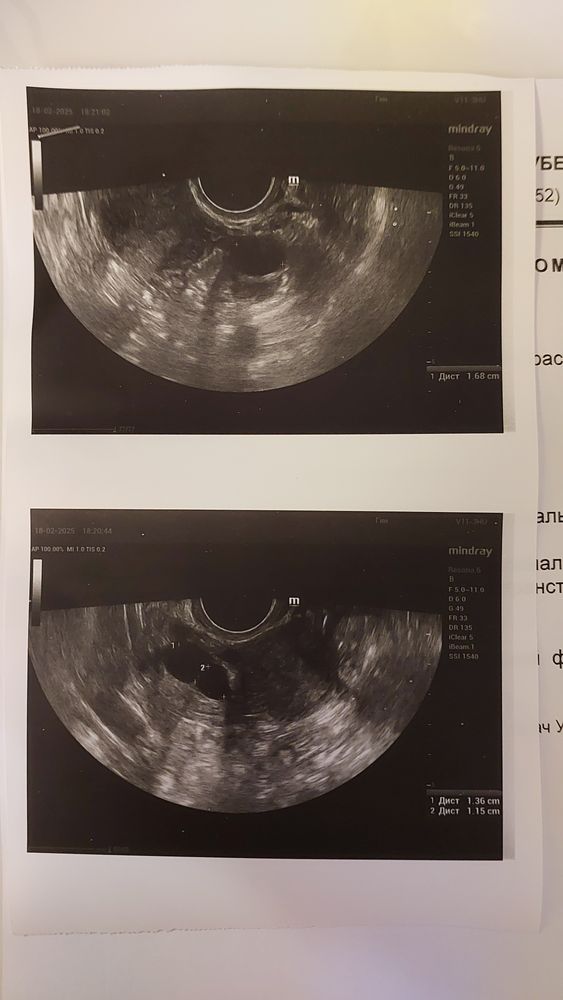

Первый раз в жизни решила попробовать стимуляцию. Но начала пить таблетки не с 5го, а с 6го ДЦ, не получилось вовремя купить таблетки. Пила по 1 таблетке утром и вечером. Итого 10 таблеток. Сходила на фолликулометрию сегодня. 3 доминантных фоликула! Причём в правом аж 2 доминанта. Хотя у меня овуляция только слева всегда. Виню себя что не начала с 5ДЦ возможно в росте они бы все были одного размера, а сейчас в левом доминант уже 17 мм, а в правом 13 и 11 мм. На 5ДЦ цикла в левом они были размером 3-4 мм и в правом 3-7 мм. Совулируют все или нет как думаете? Подскажите когда ставить укол ХГЧ 5000 ме? Сегодня 12ДЦ. На какой день начинать пить утрожестан? Какая дозировка? Купила в доз-ке 200 мг Результаты прикрепляю.

Алёнушка, я была изначально у Аветян, это ужас просто. У меня всегда 9-10 антральных, подтвержденых на УЗИ. Она мне посмотрела сказала у вас один фоликул, только платное эко с донорской яйцеклеткой. И дала прайслист на эко. Я опупела от такой наглости. Зачем мне чужой ребёнок у меня есть дочь 15 лет и мне 35 лет, а не 48. Я была в шоке это мало сказать. Там в МиД ты для них с низким запасом яйцеклеток сразу как кошелёк с деньгами. В общем я уже год проверила все что можно. У мужа нормозооспермия живые 85%, морфология 19% нормальные, вязкость норма. У меня по ЭХО ГСГ трубы обе проходимы. Цикл чёткий 28-29 дней, овуляция своя есть всегда в середине цикла. Собираю доки на квоту по эко приём в ПЦ 28 февраля. В общем я решила сделать стимуляцию клостом пока в процессе всего этого, посмотрела ответ есть на стимуляцую и это хорошо в принципе. Овуляция всегда слева, вдруг тут будет справа и получится забеременеть самой. Кстати эндометрий хороший на 12ДЦ был уже 7 мм